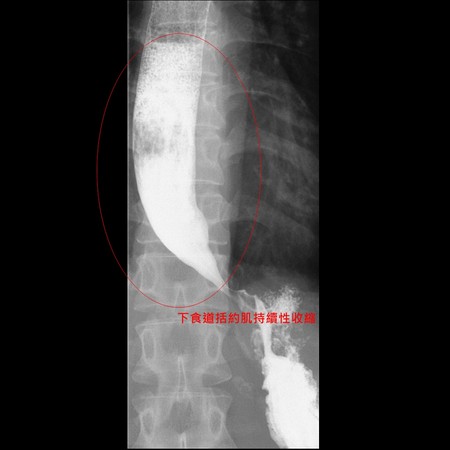

▲X光攝影發現患者食道和胃交界處呈現鳥嘴狀。

亞洲大學附屬醫院肝膽胃腸科主任陳政國表示,吳小姐到診時身高156公分,體重竟只有39公斤,經透過食道攝影檢查患者的食道,發現患者吞下藥水後,X光攝影顯示其食道和胃交界處呈現「鳥嘴狀」,且食道積滿液體無法往下流,確診為「食道弛緩不能症」。透過「經口內視鏡肌肉切開術」,切開食道肌肉,手術時間約1小時內,術後若無併發症,隔天患者即可出院,也可以順利進食。

陳政國指出,「食道弛緩不能症」通常每年20萬人約僅有1至2人罹患,好發於30歲至50歲的男性或女性,發生原因目前不明,只要因患者的下食道括約肌持續性收縮、無法放鬆,導致患者出現漸進式吞嚥困難,並伴隨胸痛、嘔吐、胃酸逆流、營養不良等症狀